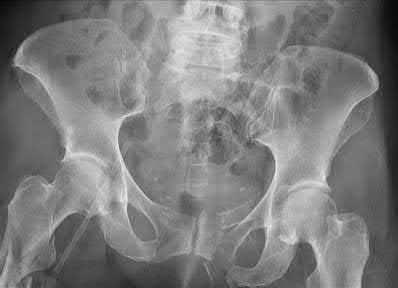

A 35 year-old female presents after prolonged extrication from a motor vehicle collision complaining of severe pelvic pain. Physical examination reveals diminished perianal sensation. She is otherwise neurologically intact. Figures A through D are radiographs and representative CT cuts of her injury. Which of the following nerve roots has likely been injured by the acute trauma?

The clinical scenario is consistent with a high-energy sacral fracture. The radiographs in figures A and B demonstrate a sacral fracture with posterior displacement of the right hemipelvis seen on the inlet view. Figures C and D are axial and sagittal CT images which show a displaced fracture of the right

hemisacrum along with a transvere fracture component through the S3 body . Diminished perianal sensation is concerning for an S2 nerve root injury.